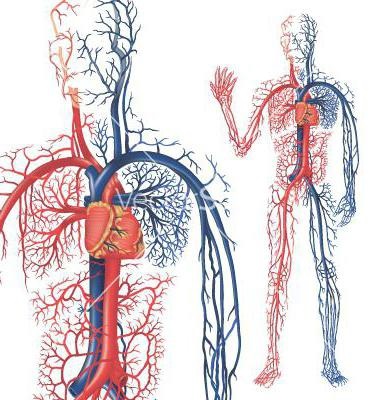

Élettani vérkeringés: a vénák, kapillárisok és az artériák

Hála a tudósok vizsgálatok tudjuk, hogy a vér folyamatosan mozog speciális üreges cső, amely különböző átmérőjű. Nem törnek le, és adja át a másikba, ezáltal egyetlen zárt keringési rendszer. Mindhárom ismert típusú vérerek: artériák, vénák, kapillárisok. Mindegyikük eltérő szerkezetűek. Az artériák hajók, amelyek a vér áramlását a szervek, a szív. Belül bélelt egyrétegű hám és a kötőszövet kívül héj. A középső réteg az artériás fal sima izom.

keringés

Minden hajó ötvözi, hogy két kört, amelyek az úgynevezett nagy és kicsi. Origin telítettsége szervek és szövetek oxigéndús vért. A szisztémás keringésben a következő: a bal pitvarba, hogy a megfelelő időben csökken, ezáltal lehetővé téve a vér áramlását a bal kamrába. Onnan a vér irányul az aortába, ahonnan az tovább mozog más artériák és arteriolák, futás különböző irányokba a szöveteket az egész szervezet. A vért, majd visszatért az ereiben, és bemegy a jobb pitvarba.

Vér és keringés: a kis kör

A második forgalomba kezdődik a jobb kamra és végződik a bal pitvarba. Mivel kering a vér a tüdőbe. Élettani vérkeringést a kis kör. Csökkentése jobb kamrai vér irányt a pulmonalis törzs, amely ágak ki a hatalmas hálózata tüdő kapillárisok. A vér, a belépő számukra, oxigénnel a tüdőventilációs, majd visszatér a bal pitvarba. Megállapíthatjuk, hogy biztosítani két forgalomban mozgását a vérben, először is irányul mentén a nagy kör a szövetekhez, és vissza, majd a kis - a tüdőbe, ahol oxigént telített. Emberi vérkeringés miatt előfordul, hogy a ritmikus szív munkája és a különbség a nyomás az artériákban és vénákban.